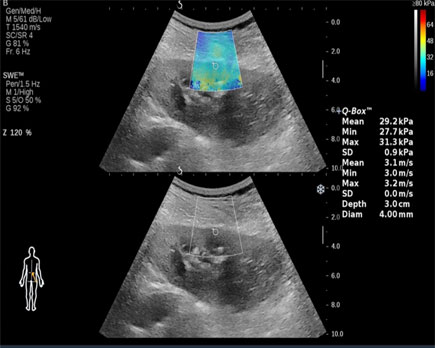

روش کار این سونوگرافی با سونوگرافی های دیگر کاملاً متفاوت می باشد. در این روش بیمار به پشت دراز می کشد سپس پروپ میکروفونی شکل مخصوص دستگاه داپلر ترانس کرانیال (TCD) بر روی سر بیمار قرار داده می شود تا امواج فراصوتی را به داخل رگهای مغز منتقل نماید و میزان سرعت و جریان خون را بررسی کند. پاسخ را به صورت صدا و تصویر در صفحه مانیتوری کوچک در اختیار پزشک متخصص قرار دهد. از آنجا که استخوان های جمجمه مانع عبور مقدار زیادی از امواج اوالتراسوند می شوند، مناطقی از جمجمه که دارای ضخامت کمتری هستند و کمترین اعوجاج را نسبت به این امواج دارند (به نام پنجره های انسداد)، باید برای تجزیه و تحلیل استفاده شوند، به همین دلیل، اندازه گیری در ناحیه ای بالاتر از قوس گونه، از طریق چشم، زیر فک و از پشت سر انجام می شود.